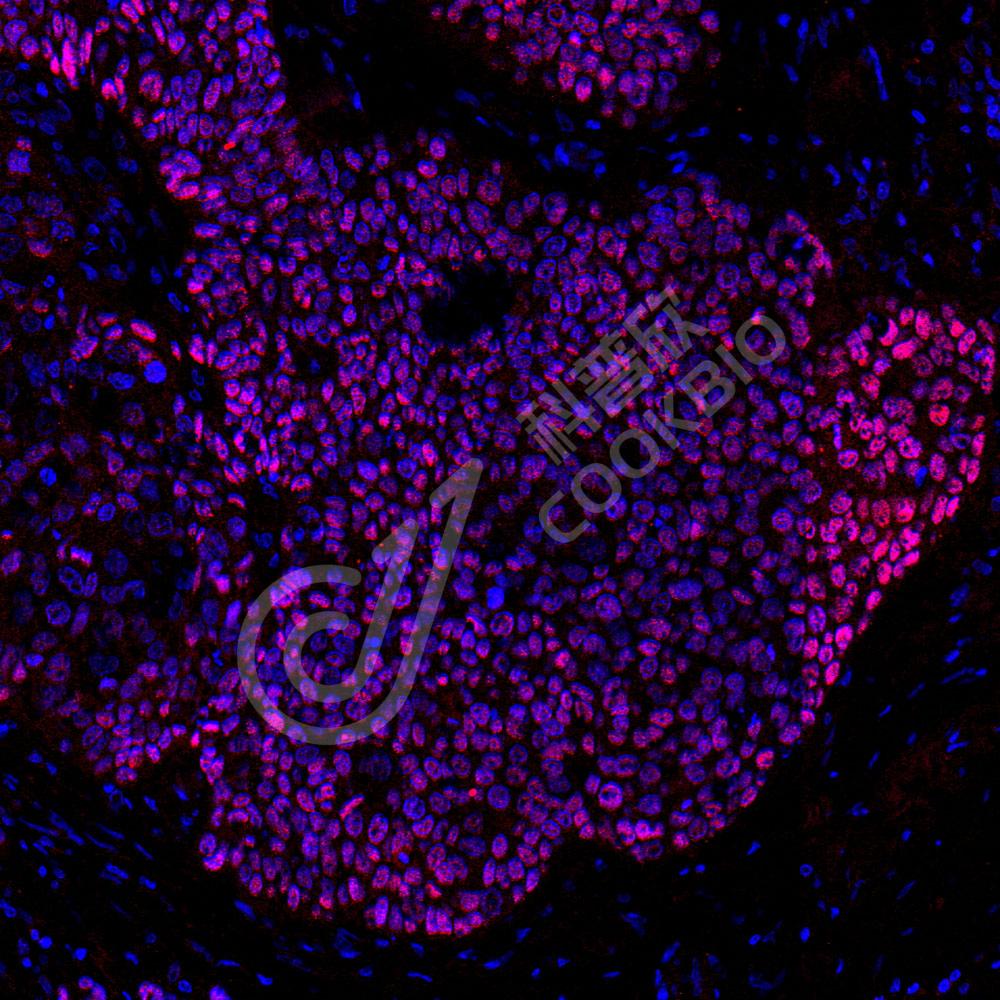

IF检测p40-DeltaNp63蛋白(货号 K5450009)(红色).

样品: 人食管癌, 4%多聚甲醛 (货号KSG1101) 固定12-24小时.

抗原修复: 柠檬酸抗原修复液(干粉, pH 6.0) (KSG1201), 高压锅均匀喷气计时2分钟.

封闭: 3% BSA(货号KSGC305010)的PBS溶液, 室温孵育30分钟.

—抗: 1: 1300稀释, 4℃ 孵育过夜.

二抗: Cy3标记山羊抗兔IgG (H+L) (货号KB63909), 1: 300稀释, 室温孵育1小时.